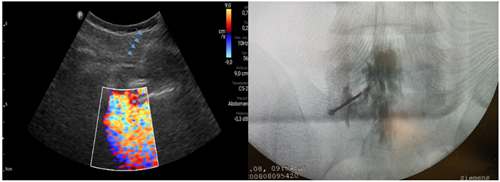

Pacientes y métodos: Un total de 25 pacientes con dolor radicular lumbosacro fueron seleccionados para recibir inyecciones epidurales interlaminares de esteroides en posición decúbito dorsal, utilizando la técnica ecoguiada en plano, en tiempo real, en eje corto o transversal. En todos los casos, un epidurograma de control fue realizado previo a la inyección de la solución de esteroides. El rendimiento de la técnica fue estudiado mediante la tasa de éxito de la misma, entendido como éxito a la obtención de un epidurograma sin necesidad de abandonar la técnica ecográfica en un tiempo menor a 10 minutos. El rendimiento del procedimiento fue estadísticamente evaluado por el método de la suma acumulativa (CUSUM), y la curva de aprendizaje aplicando este método fue construida.

Resultados: La distancia promedio desde la piel al complejo posterior evaluada por el escaneo ecográfico previo al procedimiento fue de 6,7 ± 1,8 cm. De los 25 procedimientos realizados, en 21 se alcanzó el espacio epidural sin ayuda de la fluoroscopia, en un tiempo promedio de 4,8 ± 1,2 minutos. Esto constituye una tasa de éxito del 84 %. En los cuatro procedimientos restantes el espacio epidural fue alcanzado con éxito mediante el uso complementario de la fluoroscopia.

Figura 1

Figura 2